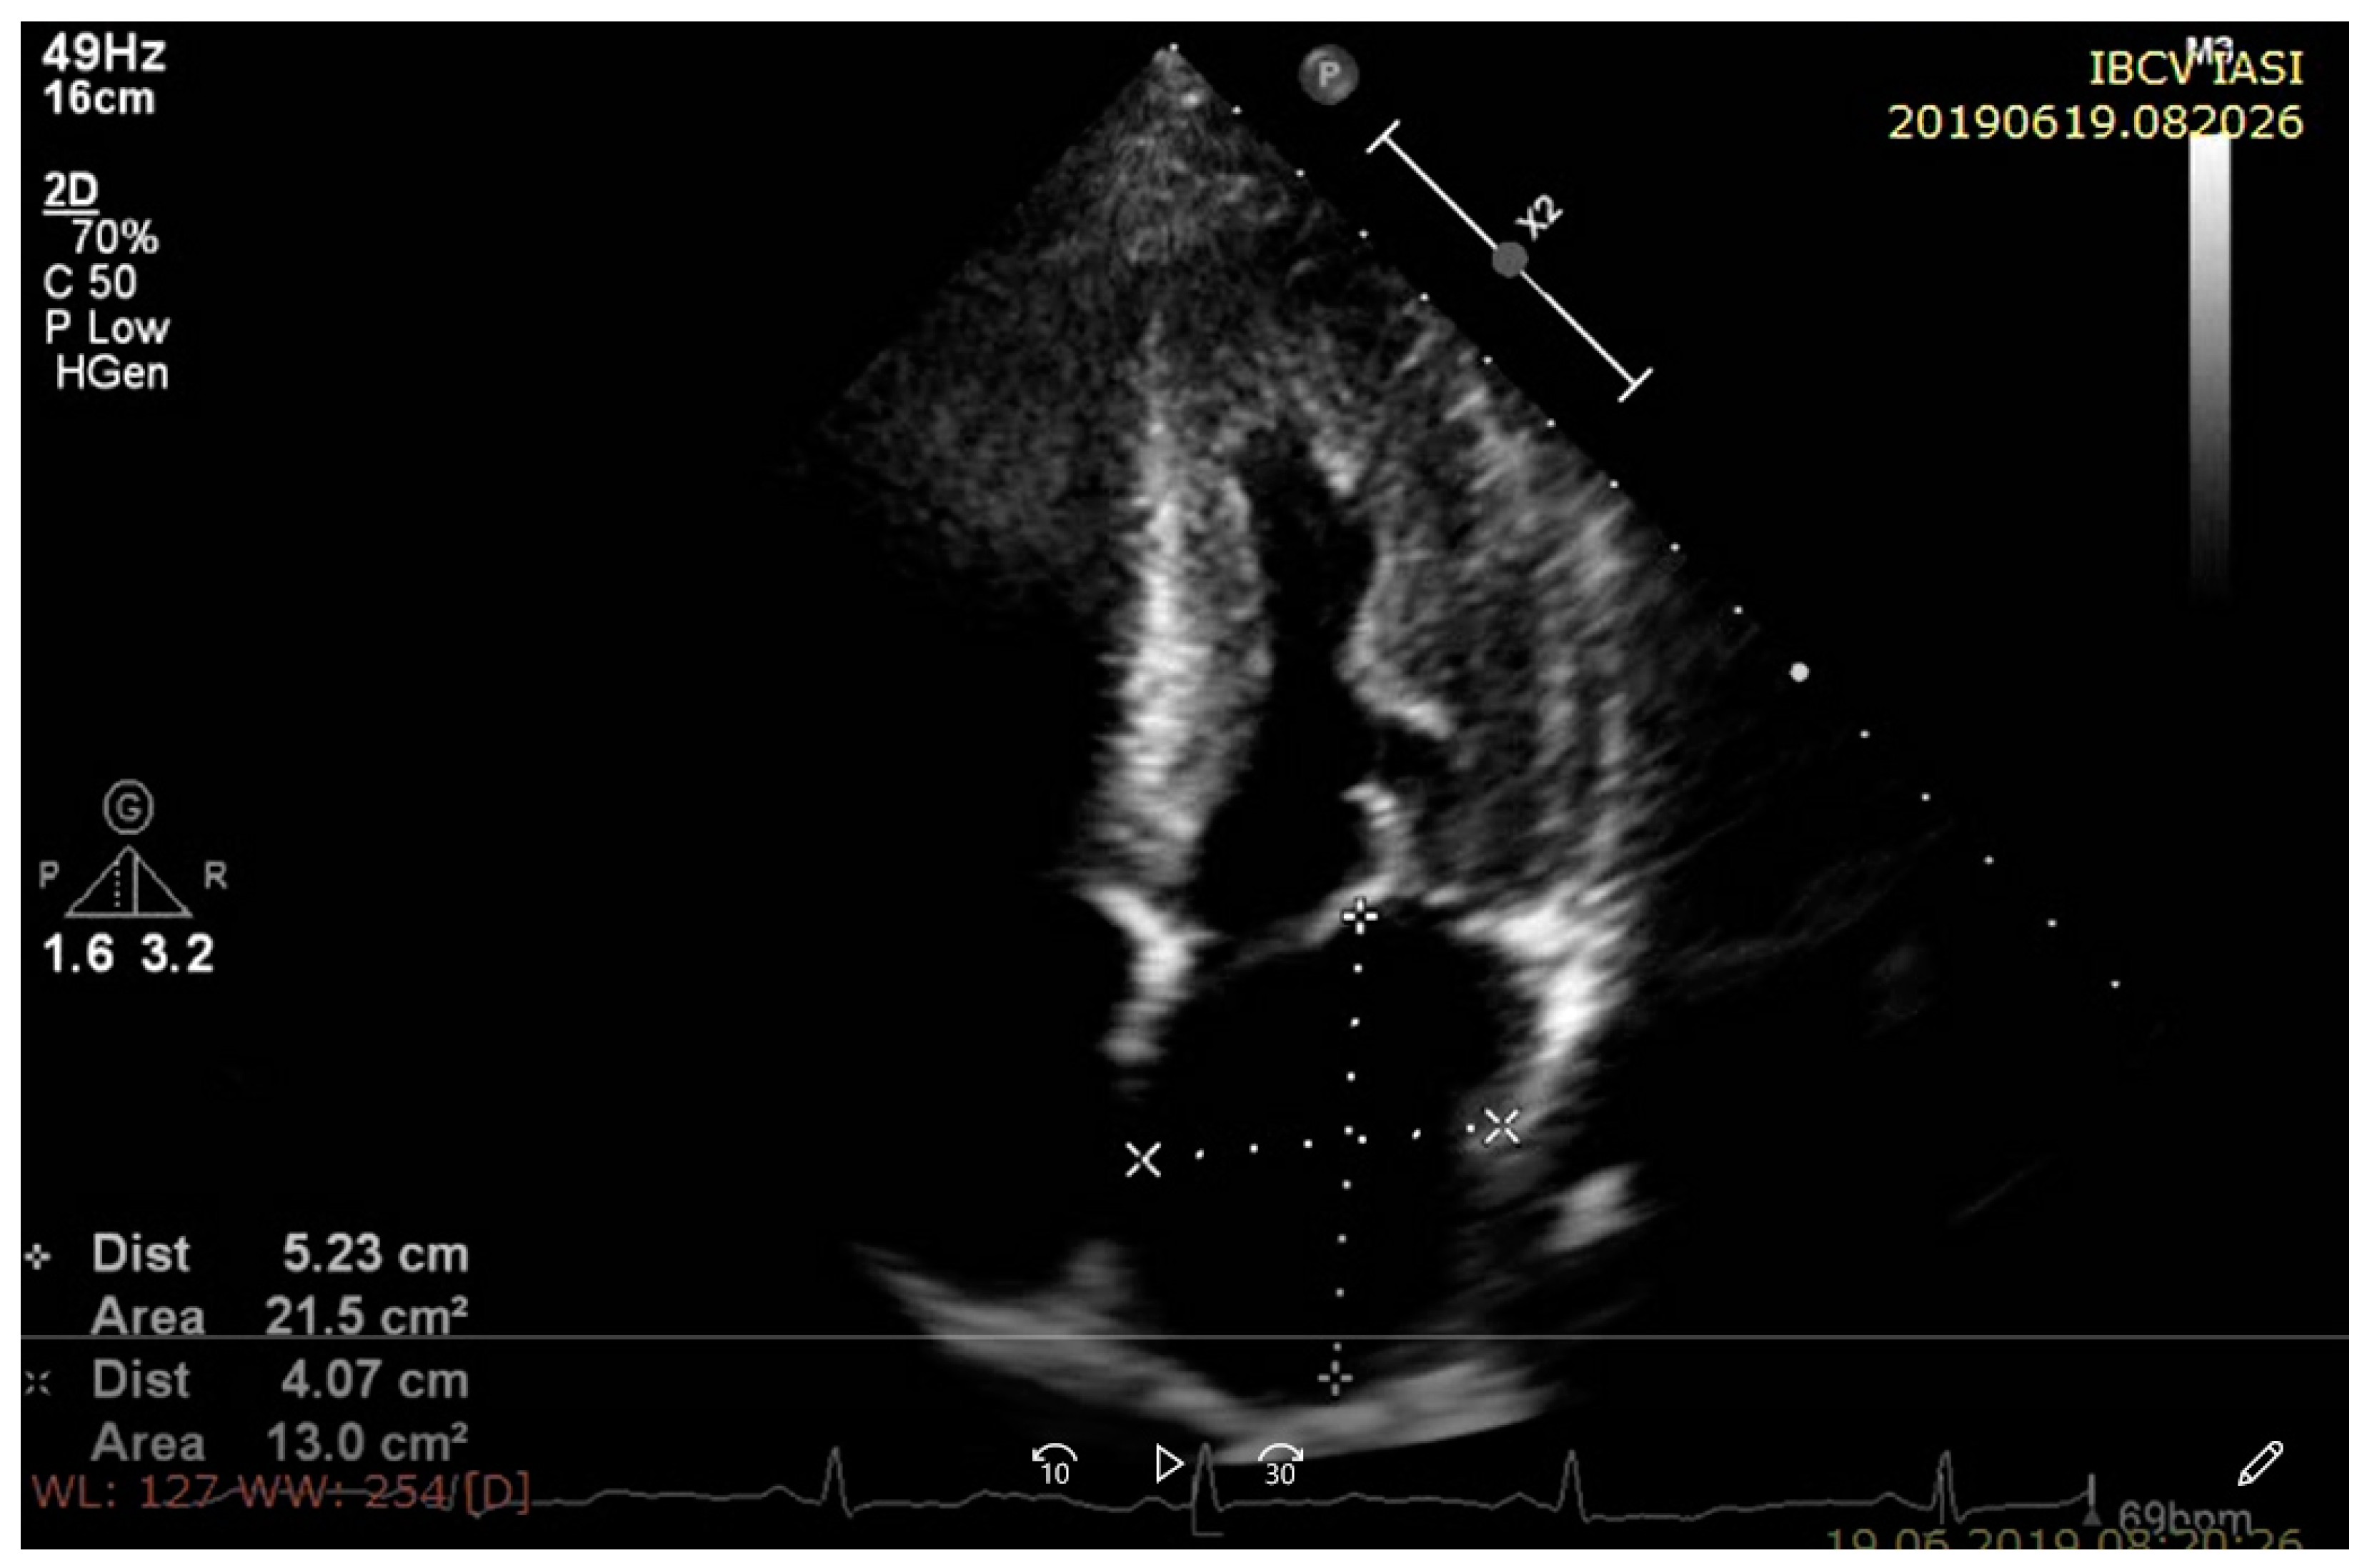

2. Conventional Transthoracic Echocardiography (TTE)

2.1. Left Ventricular Wall Thickness and Cavity Size

2.1.1. Left Ventricular Wall Thickness and Cavity Size in Amyloidosis